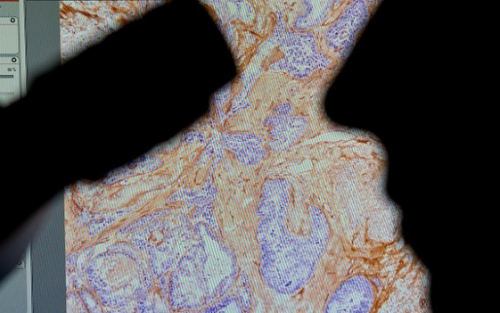

近来有 2 项相关研究显示肠道菌对抗癌的可能潜力,2015 年 11 月时,芝加哥大学的一项研究显示,给予小鼠正常肠道菌双歧杆菌,对皮肤癌成长的抑制效果,与给予免疫疗法相当,而同时给予双歧杆菌与免疫疗法,则消灭了皮肤癌;另一项法国的研究显示,有些肠道菌菌种,具有活化免疫疗法反应的作用,若没有这些菌种时,免疫疗法将无法启动。

许多国际大药厂也已经注意到人类微生物群系在当前极为热门的癌症免疫疗法上的影响,过去在小鼠实验时,经常发现明明是基因完全相同的小鼠,对免疫疗法药物的反应却有所不同,合理的解释是两只小鼠虽然细胞基因都相同,但是身上的微生物群系却不同,才造成对药物的反应不同,如今包括罗氏大药厂(Roche)、阿斯特捷利康(AstraZeneca)、必治妥施贵宝(Bristol-Myers Squibb)、美国默克药厂(Merck & Co.)都十分关注此领域的发展。